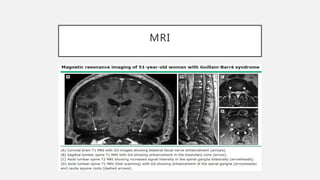

MRI

• Gadolinium enhancement of nerve roots.

• To eliminate transverse myelitis, subacute

compressive myelopathy, and infiltrating illnesses of

the roots and the spinal cord.

• 95% of children with GBS show enhancement of the

lumbar roots.